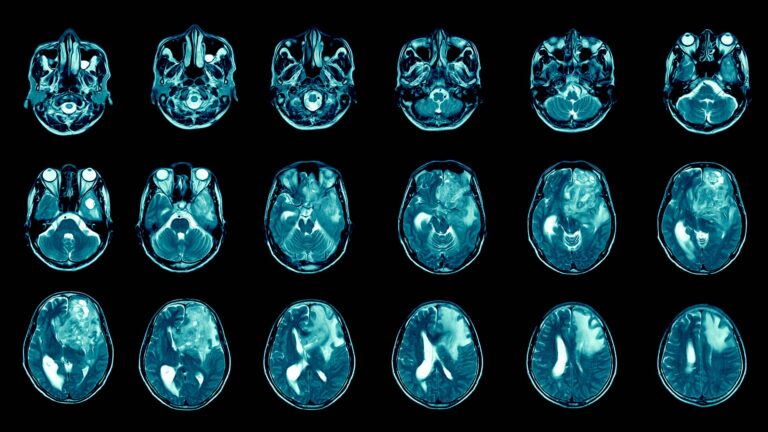

Understanding fundamental cellular processes that are the basis of life, and how they go wrong in cancer. Improving diagnosis and treatment of all major cancers: brain, breast, colon, leukemia, lung, lymphoma, melanoma, ovarian, pancreatic, and prostate.

Exploring the brain to identify the neural networks involved in sensory processing, cognition, and decision-making. Providing insight into disorders such as Alzheimer’s, autism, schizophrenia, bipolar disorder, and depression.